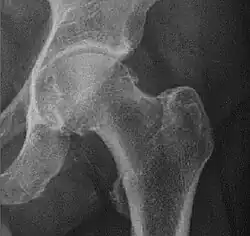

X-ray of the hips of a 40-year-old female, with dysplasia of her right hip.